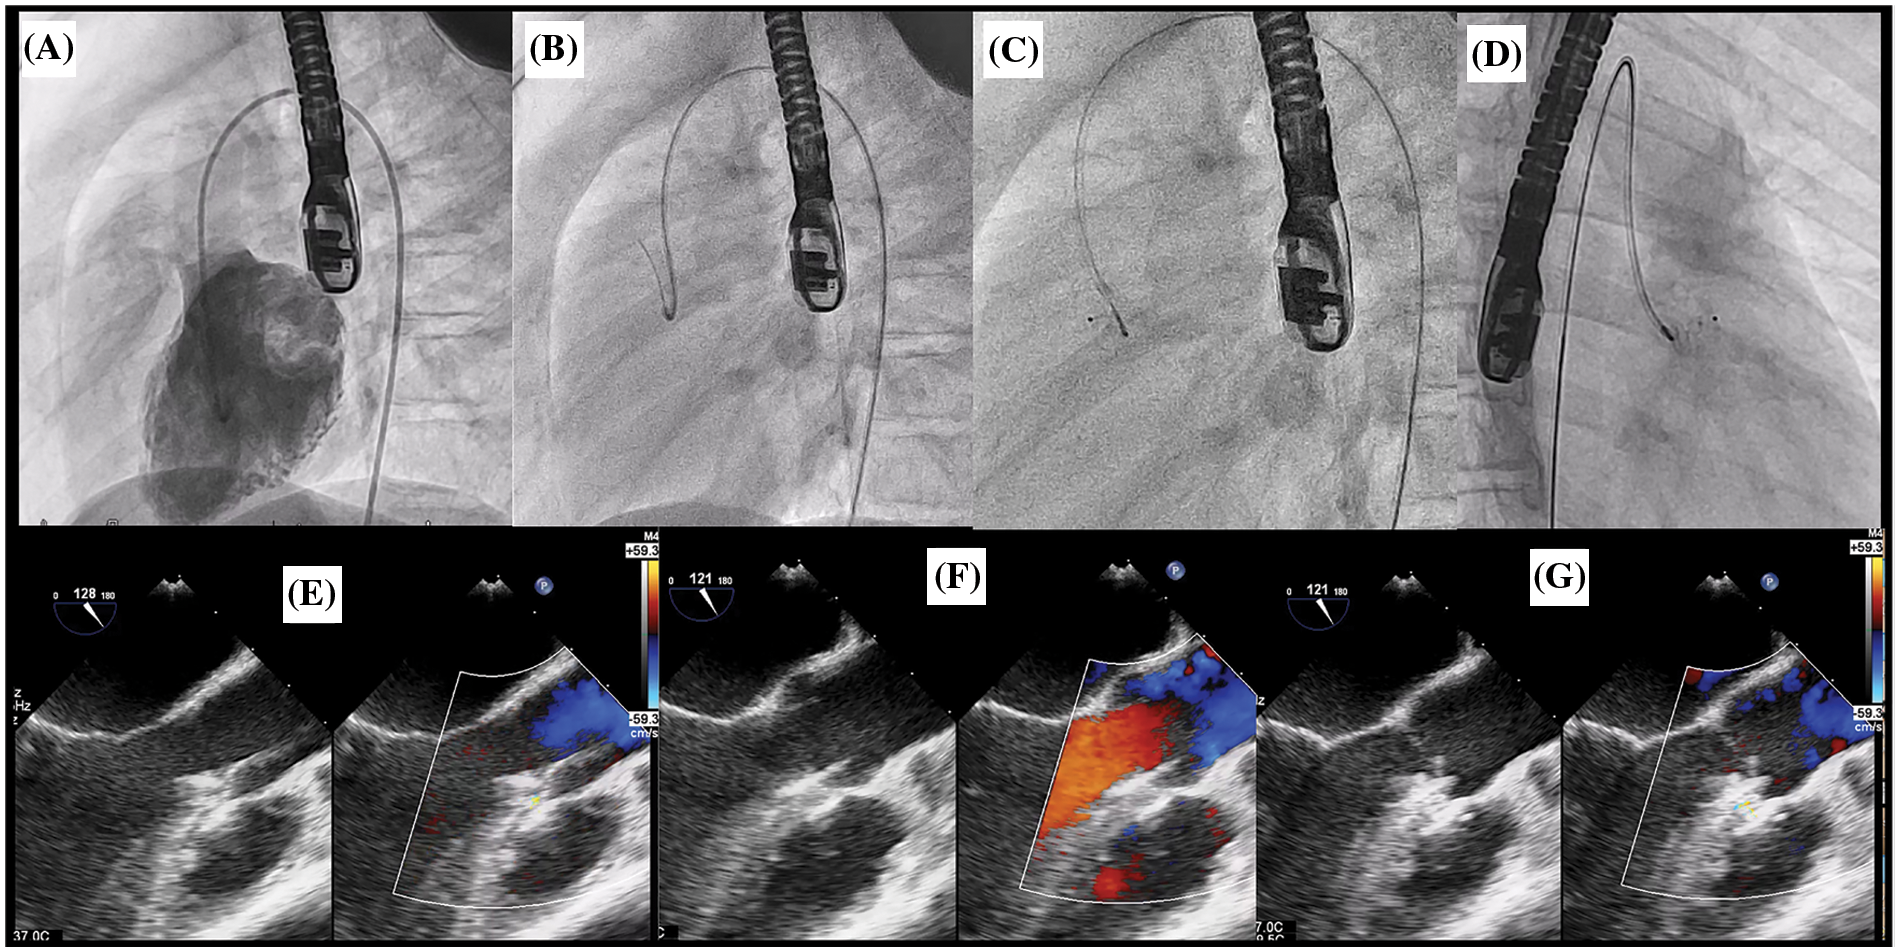

For retrograde approach (Fig. 4), after successful VSD crossing, the guidewire tip shall be placed as distal as possible to the right or left pulmonary artery branch. Subsequently, with the support from deeply seated guidewire, the 5 Fr Torque LP or 6 Fr Mullin delivery sheath was gently introduced across the defect to place at the mid RV chamber. The device was loaded and advanced to the tip of the sheath and deployed the RV disc in the RV. With echocardiographic and fluoroscopic guidances, the whole system was meticulously pulled back toward the ventricular septum. Once the RV disc well opposed to the VSD, the body and the LV disc were deployed. In order to minimize the tension to the aortic valve causing AR, the delivery system was pulled back into the ascending aorta and the delivery cable was gently pushed to coaxially align the LV disk to the VSD.

Figure 4: Retrograde approach for OVSD closure. (A) The LV angiogram showing a contrast jet of OVSD beneath the aortic valve in lateral view. (B) Crossing VSD by cut pigtail (180°) over terumo glidewire to the RV. (C), (D) ADO II 3/4 was implanted through the retrograde grade approach in lateral and right anterior oblique 30°, respectively. E: TOE after deploy ADO II device while delivery cable remain attachment. (F), (G) TOE after releasing the device in systole and diastole phase respectively showing no residual shunt and no AR

Repeated LV angiography and TOE (in 30°–45° and 75°–120°) were performed after deployment to evaluate residual shunt, device stability, evidence of RVOT/LVOT obstructions, and disturbance of the aortic and pulmonic valve function. In retrograde approach, trivial AR may be visualised from TOE since the delivery cable was still attached to the device. Nonetheless, with sleek design of the delivery cable, the disturbance of aortic valve function was minimal. Therefore, AR severity more than trivial at this stage was unacceptable. After obtaining satisfactory results, the device was released. Then, the LV angiography and TOE were conducted for final assessment.